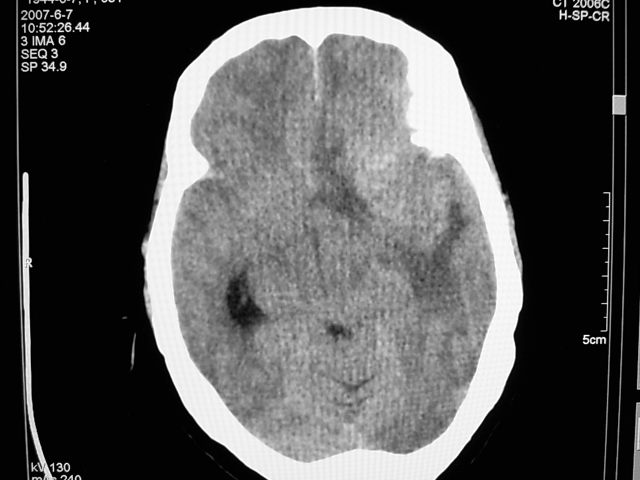

患者 女 63岁,近几周感觉头部不适来查体。

请调骨窗。多考虑前中颅窝脑外肿瘤,脑膜瘤、淋巴瘤或血管外皮瘤均有可能,蝶嵴脑膜瘤可能性最大。

左侧额颞部巨大肿块,平扫呈略高密度,增强明显强化,周围水肿明显,左侧侧脑室受压,右侧侧脑室扩大,中线明显右移,局部骨质增厚,支持脑膜瘤、大脑廉下疝。